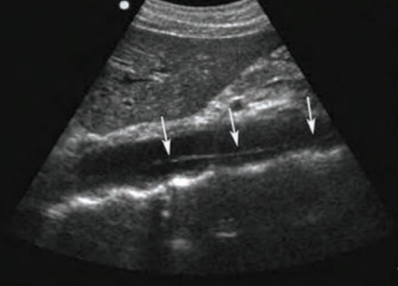

scanning techniques for imaging AO

pt. supine or slightly decubitus

anterior or coronal approach

curvilinear probe

measure outer-to-outer wall; low to medium gain (to show walls but no lumen artifact)

use breathing technique or “push belly out”